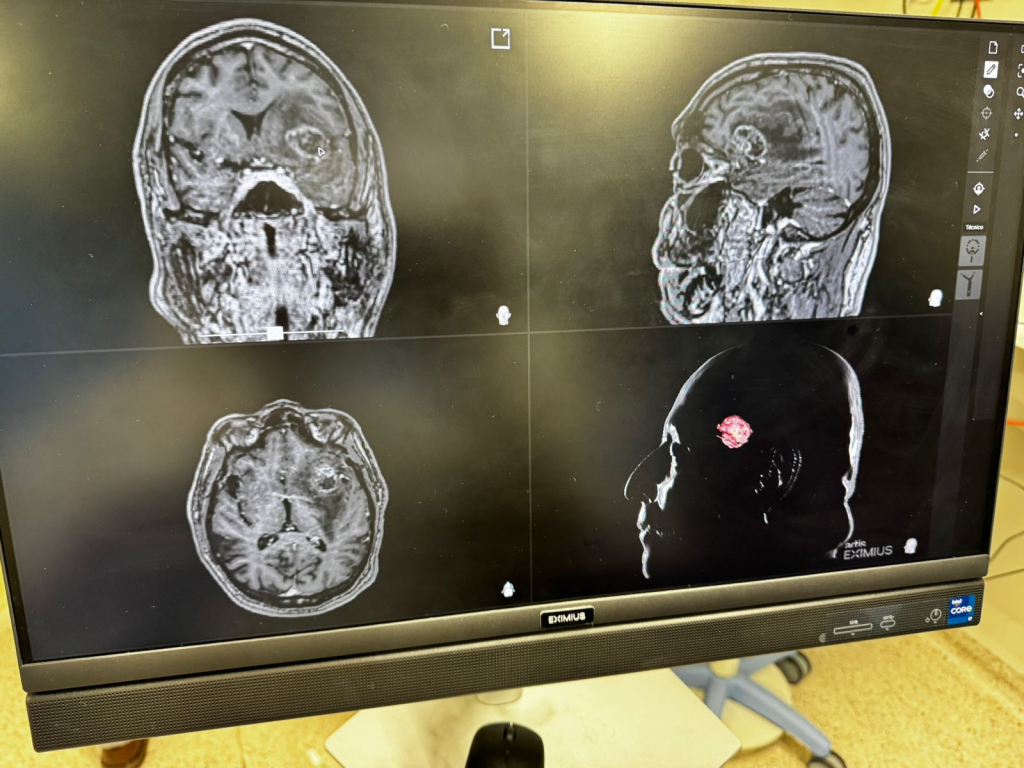

Essa precisão é reforçada pelo uso da neuronevegação, uma tecnologia de ponta disponível na Cassems que funciona como um GPS intracraniano. Através de uma ponteira laser, o médico consegue localizar a lesão com exatidão milimétrica na ressonância em tempo real. “Isso diminui muito o quanto a gente manipula o cérebro, agindo apenas na área estritamente necessária”, pontua Zanin.

Diferente das cirurgias convencionais, manter o paciente consciente durante parte da operação não é apenas um detalhe técnico, mas uma estratégia de segurança. A técnica é empregada em casos específicos onde a lesão cerebral está situada em “zonas eloquentes” — áreas responsáveis por funções vitais como a linguagem e a motricidade. O objetivo central é proporcionar uma ressecção máxima da lesão com o mínimo de risco funcional.